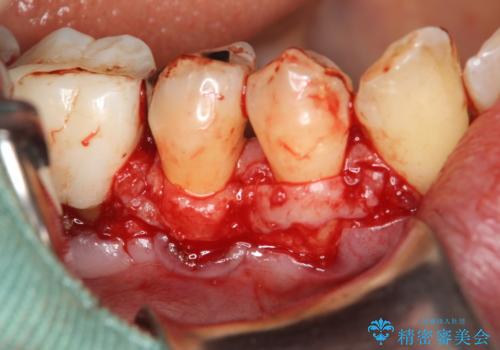

- 右下4番と5番に丈夫な歯肉が不足しているために、徐々に歯肉が下がってきていたケースです。

これ以上の歯肉退縮を防ぐべく、丈夫な歯肉の獲得を目的として結合組織移植術による対応を行いました。

患部にはごくわずかに丈夫な歯肉(角化歯肉)がある状態でした。この丈夫な歯肉の幅を十分に増大させ、厚みを持たせる事で、ブラッシングによっても下がりにくく安定した状態となります。

術式は歯冠側移動術と歯肉結合組織移植術を併用しました。